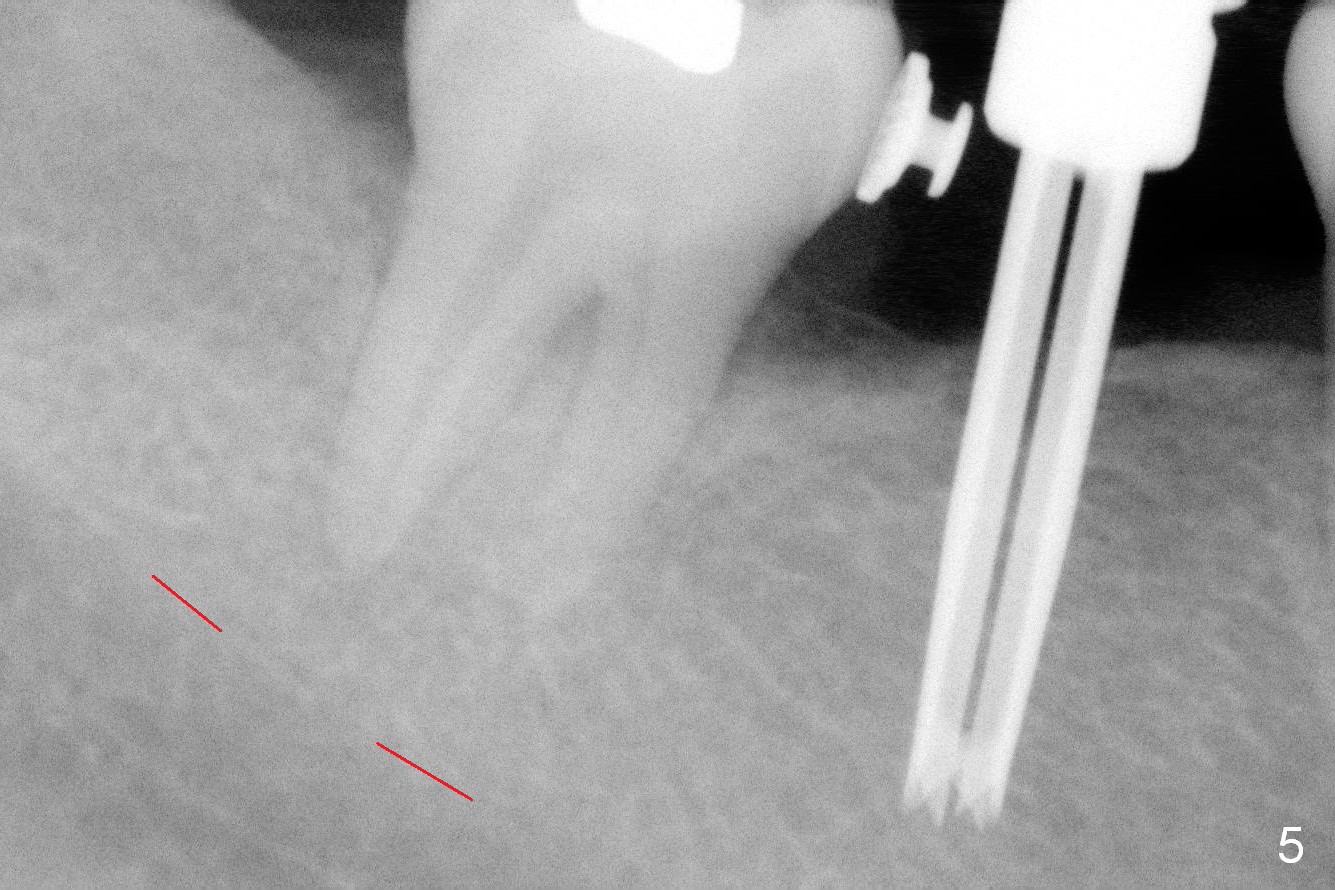

The ridge is found to be fairly narrow after incision. Bone density is determined to be high using #15 blade. A 1.6 mm pilot drill is used to initiate osteotomy (Fig.4). The latter is moved mesially. By the time 3.3 mm Magic Drill is in place, the osteotomy is in the better position mesiodistally (Fig.5). The same is a 4x11 mm IBS implant (Fig.6, >55 Ncm). The lingual button in the mesial of #31 is then removed, because it appears to interfere with placement of a 4.5x4(2) abutment. The position of #31 is maintained by open coil spring.